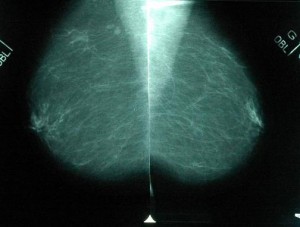

La mammographie est une radiographie des seins qui permet d'obtenir des images de l'intérieur du sein à l'aide de rayon x et de diagnostiquer d'éventuelles cancers ou anomalies.

Deux radiographies par sein sont réalisées, une de face et une autre en oblique ce qui permet de comparer les deux côtés de chaque sein.